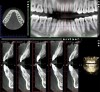

Figure 3 through Figure 8 illustrate an SFOT case where expansion and decrowding were achieved. Although increased osseous thickness was gained mostly at the apical portion of the teeth, these images clearly demonstrate that stable and robust gingival margins were established post-orthodontic treatment. This case also shows that the simultaneous use of grafting allows prevention of tissue loss that typically occurs with significant decrowding and expansion.20